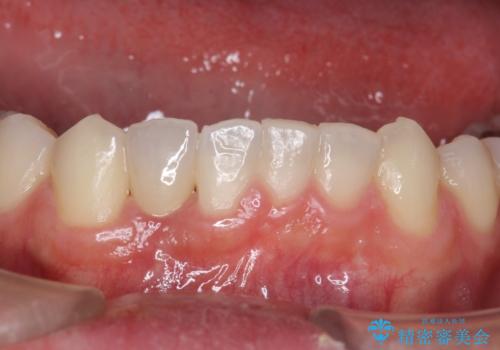

ブリッジにすることも可能でしたが、両側の歯が天然歯であること、また、事前に矯正で噛み合わせを整え、幅も確保していたこと、CTにより骨の厚みがある程度あったことを踏まえ、インプラントも可能であるとお話しし、選んでいただきました。

唇側の骨増成もしっかり行い、前歯部インプラントによくある、歯茎が下がって見えることもない、審美的なインプラント補綴ができました。